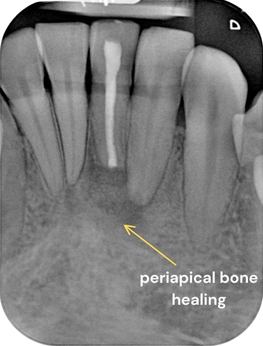

- Review after 3 months.

The patient is currently asymptomatic. As adjacent teeth 32 and 41 were non responsive after surgery, these 2 teeth are scheduled for RCT.

Review in 3 months

Testing the sensibility of adjacent teeth 32 and 41 (it was negative post surgery)